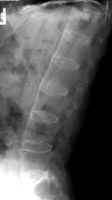

Anterior and lateral radiograph of the lumbar spine which reveals near complete fusion of all of the vertebral bodies. Spinal changes which include squaring of the vertebral bodies and fusion between adjacent levels. The fusion is secondary to syndesmophytes and resembles a bamboo stalk. This is most commonly found in ankylosing spondylitis.

AP spine - Click on the image for a larger versionALateral L-spine - Click on the image for a larger versionB